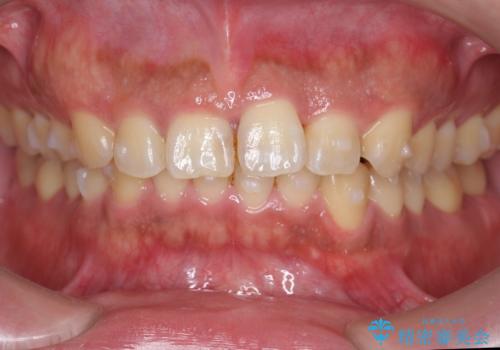

前歯のねじれを 1年かけずに矯正 インビザライン

- 前歯のねじれを主訴に来院。

インビザラインで治療しました。

前歯のねじれをセラミックで治そうとすると、抜髄といって、神経の治療が必要になる上、歯の幅も制限が出て理想的にはなりません。

保定の必要がありますが、天然歯を並べる矯正治療では、治療後の心配事が非常に少なく、保存的な処置となります。